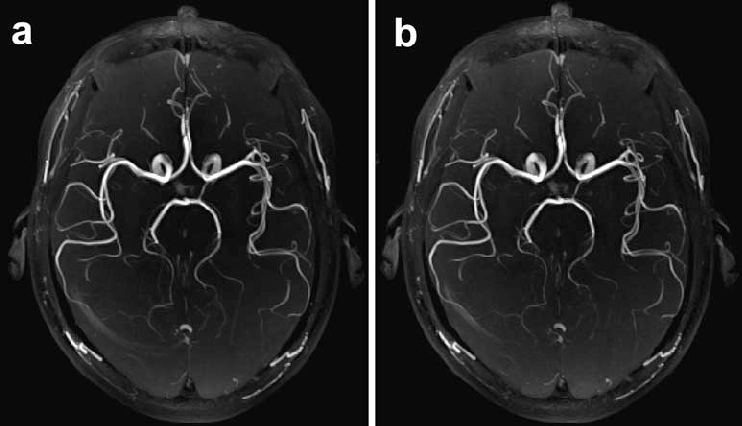

Time of Flight (TOF) applications

A specialised imaging technique of visualising blood vessels without contrast

Applications:

TOF MRA is commonly used to diagnose conditions like intracranial occlusions, aneurysms, and arteriovenous malformations